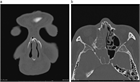

1. X線画像検査で大方の骨折は診断が可能である。